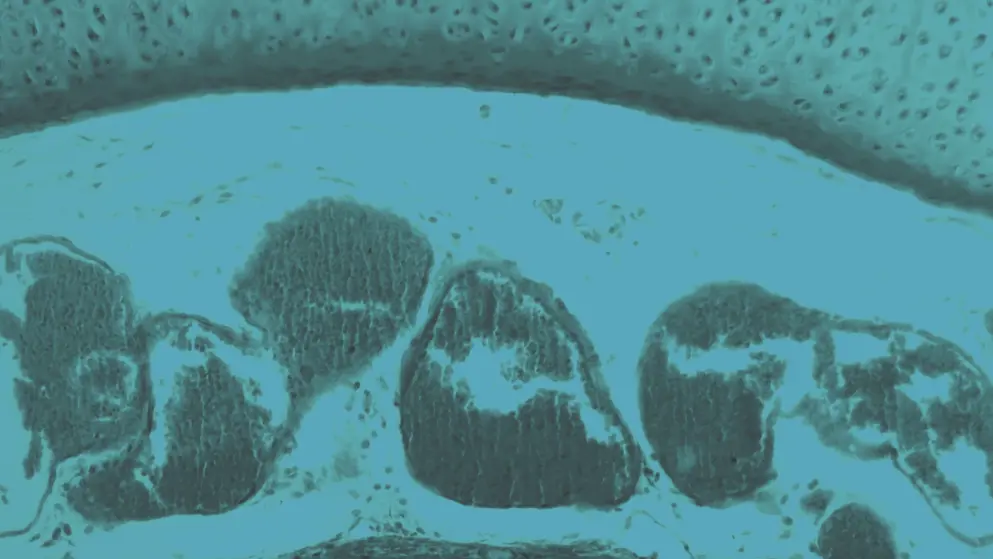

Trachea Cells under the Microscope, cell image, blue overlay